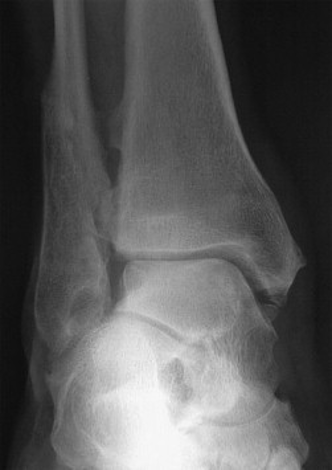

Mekanik Kemik Instabilitesi: Osteokondral değişikliklerin yanı sıra bazı ayak morfolojileri de instabiliteye neden olabilir. Bu bağlamda, lateral malleol’un pozisyonu önemlidir ve anterior talofibular bağın uzaması veya kopmasıyla posteriora kayabilir.

Şekil 8. Fibular malleolun malunionu: lateral rotasyon ve diastaz.